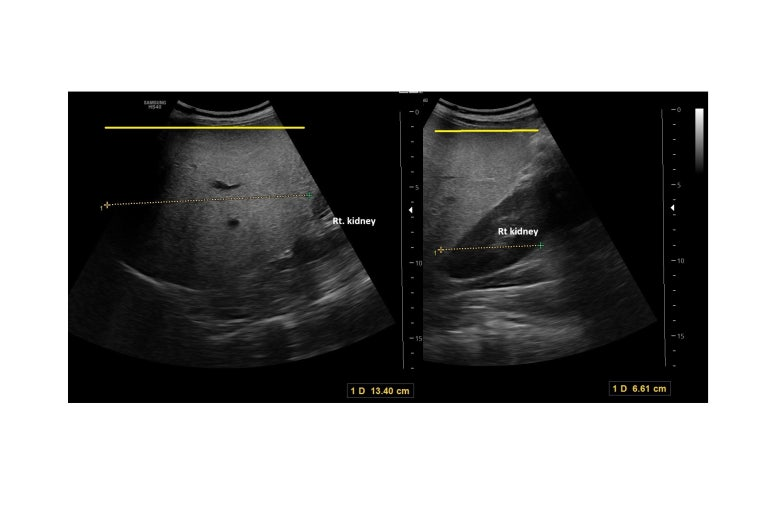

renal ultraound

midclavicular line averages 10-12.5 cm in craniocaudal length 2

a liver that is longer than 15.5-16 cm in the midclavicular line (MCL) is considered enlarged